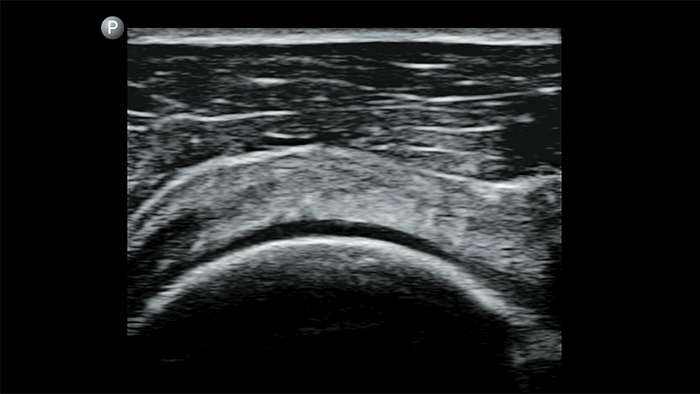

Use Lumify for airway and pulmonary assessment

Lumify POCUS solutions can help you detect the endotracheal tube within the trachea, assist in emergent cricothyrotomy procedures, diagnose pleural effusion and interstitial alveolar diseases.